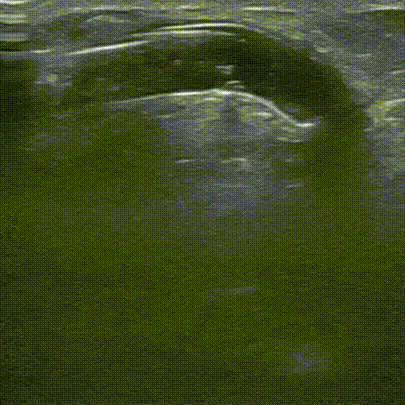

术前肱动脉血流量272.9ml/min。